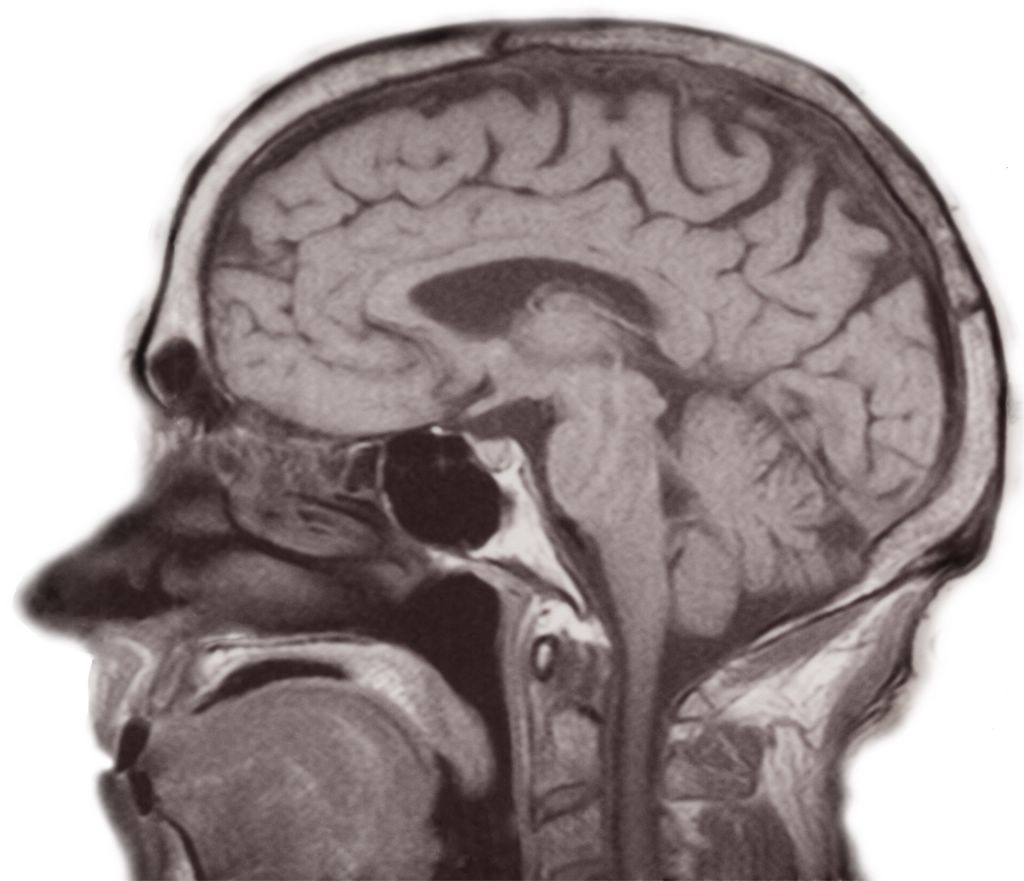

Brains -- mri_10_(was_11).jpg